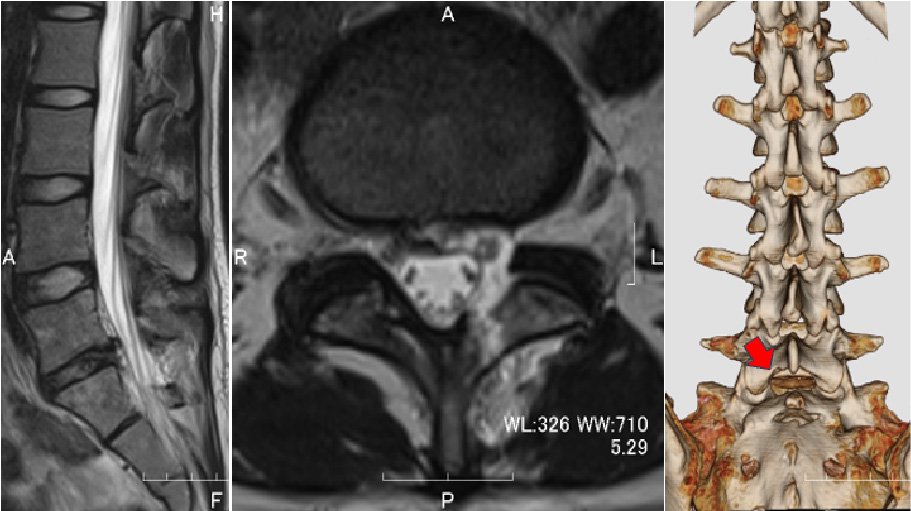

術前MRI:大きなヘルニア

(左図の矢印、右図の丸印)

を認め神経を強く圧迫しています

術後:ヘルニアは完全摘出され、神経の圧迫が解除されています。

右図は背中から見た腰椎を示していますが、

少量の骨削除による開窓でヘルニアが摘出されました。